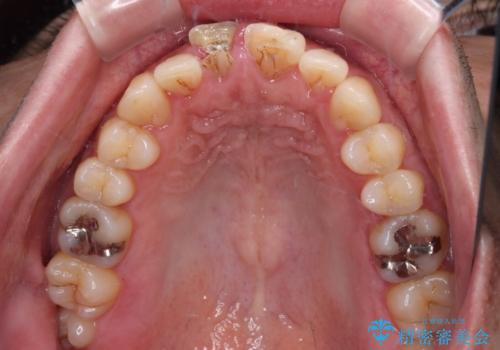

- 転倒により前歯を折ってしまったとのことで来院された患者様です。

右側の前歯は歯茎の中にまで及ぶ深い破折線があり、神経組織は既に失活していました。

左側の前歯は大きく歯冠が欠けてはいましたが、神経の生活反応が認められました。

失活した歯は、根管治療を行った後に部分矯正により歯根を引っ張り出し、歯周外科処置により左右の歯肉の位置が揃えることとしました。